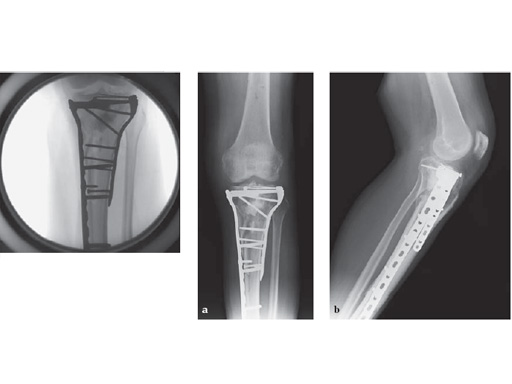

The LCP Medial Proximal Tibia Plates 3.5 and 4.5 are part of the LCP periarticular plating system. They are intended to buttress metaphyseal fractures of the medial tibia plateau, split-type fractures of the medial tibia plateau, medial split fractures with associated depressions and split or depression fractures of the medial tibia plateau. The plates may also be used for fixation of the proximal quarter (lateral and medial) of the tibia as well as segmental fractures of the proximal tibia. The 4.5 version may also be used for fixation of nonunions and malunions of the medial proximal tibia and tibia shaft, as well as opening and closing wedge tibial osteotomies.

The plates have a limited contact profile. The plate head is anatomically contoured to approximate the anteromedial proximal tibia. The plates feature 3 locking screw holes proximally, with trajectories parallel to the joint. These proximal locking head screws also converge in the lateral condyle. The 2 angled locking screw holes in the proximal part of the shaft converge with 2 of the proximal screws in the head of the plate.

The 3 convergent threaded screw holes in the head of the plate 4.5 accept 5.0 mm cannulated locking and 5.0 mm cannulated conical screws, while the plate 3.5 accepts 3.5 mm locking and 3.5 mm conical screws. The screw-hole pattern allows a raft of subchondral locking head screws to buttress and maintain reduction of the articular surface. This provides fixed angle support to the tibial plateau. Additionally, there are two 2.0 mm K-wire holes available for preliminary fixation with K-wires or meniscal repair with sutures.

57-year-old malemotor accident

Case provided by Phil Kregor, Nashville, USA